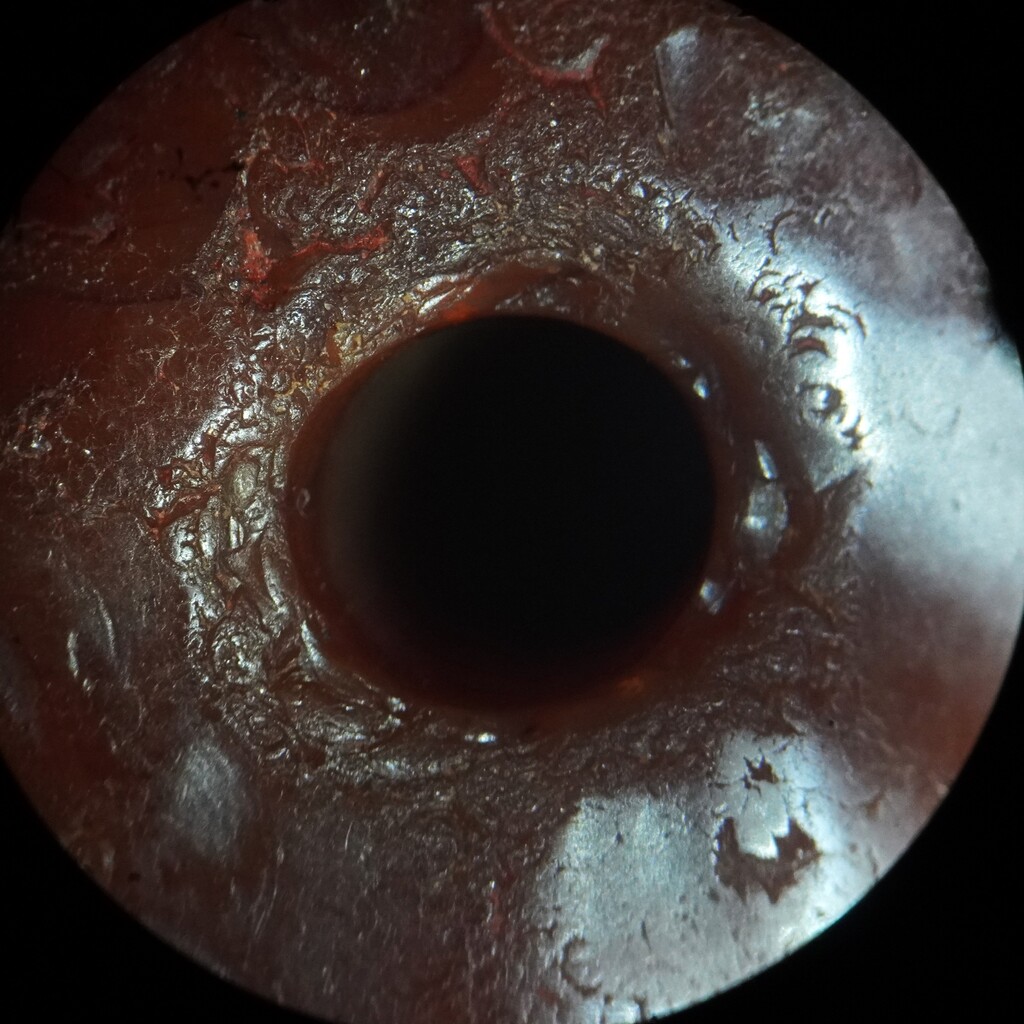

甸的神玉髓古珠.

出土文物.地埋古珠.

不的八角型珠.

有.斑沁..洞.瑙虹化...等地埋特徵

有3手指和神生物部.特殊造型的古珠.